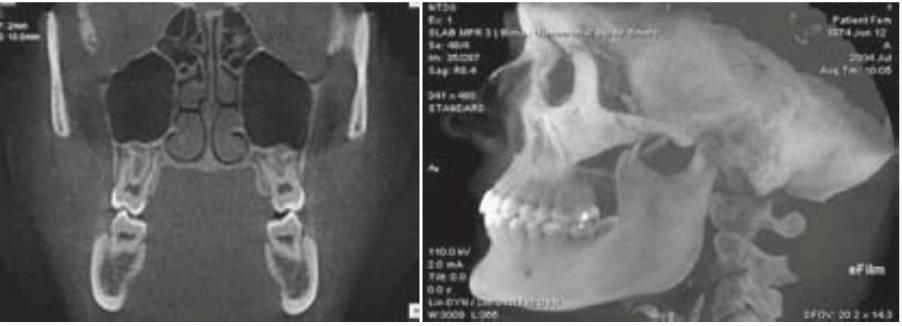

El poder y la utilidad del TC en la imagen y el diagnóstico maxilofacial se volvieron evidentes tan pronto como se introdujeron los TC de alta resolución a principios de la década de 1980. La TC se empleaba para producir imágenes de la articulación temporomandibular, la evaluación de lesiones dentales/óseas, la evaluación de las deformidades maxilofaciales, y la evaluación preoperatoria y postoperatoria de la región maxilofacial. La TC proporciona unos medios únicos de análisis postimágenes de la cirugía propuesta o de los lechos implantológicos reformateando el dato de la imagen para crear imágenes tomográficas tangenciales y de cortes de sección del sitio del implante. Con los escáneres TC de actual generación, las imágenes reformateadas se caracterizan por un espesor de sección de 1 pixel (0,25 mm) y una resolución de plano in terno de 1 pixel por la distancia de barrido (0,5 a 1,5 mm), produciendo una resolución geométrica similar al de una imagen plana. La densidad de las estructuras dentro de la imagen es absoluta y cuantitativa y puede emplearse para diferenciar los tejidos en la región y caracterizar la calidad ósea (fig. 3-10; cuadros 3-8 y 3-9).

La TC permite la evaluación de los lechos implantológicos propuestos y proporciona in formación diagnóstica que otras técnicas o combinaciones de técnicas de imagen no pueden proporcionar. La utilidad de la TC para la planificación del tratamiento de implantes dentales56'62 era evidente, pero el acceso a estas técnicas de imágenes era limitado. El acceso a esta in formación diagnóstica requería un radiólogo para comunicar a los doctores referidos con detalle a propósito de la cirugía prospectiva y para sentarse delante del ordenador de imagen o de la estación de trabajo durante un lapso considerable de tiempo para reformatear el estudio, interpretar las imágenes resultantes, y producir copias en soporte duro de las imágenes para enviarlas a los doctores referidos. Las ventajas de este tipo de imágenes eran evidentes así como las limitaciones de su transmisión, lo que derivó en el desarrollo de un número de técnicas a las que nos referimos genéricamente como imágenes DentaScan.

Las imágenes DentaScan proporcionan una reforma, organización e imagen en pantalla programadas del estudio de imágenes (fig. 3-10). El técnico o el radiólogo simplemente indica la curvatura del arco mandibular o maxilar, y el ordenador es programado para generar cortes de sección referenciados e imágenes tangenciales/panorámicas de los alveolos junto con imágenes tridimensionales del arco. Las imágenes de cortes transversales y panorámicos están espaciadas entre sí 1 mm y permiten una planificación del tratamiento prequirúrgico exacto.

Las limitaciones de las imágenes DentaScan incluyen imágenes que pueden no ser verdaderas en tamaño y requieran compensación de la magnificación, la determinación de la calidad ósea que requiere el empleo de ordenadores o estaciones de trabajo de imágenes, copias en soportes duros de imágenes DentaScan que solo incluyen una parte limitada de la escala de grises diagnóstica del estudio, y la inclinación de la cabeza del paciente durante el examen, lo que es crítico ya que todas las imágenes de corte de sección son perpendiculares al plano axial de la imagen. Esta técnica proporciona una información diagnóstica abundante que es exacta, detallada y específica. normalmente es necesaria una plantilla diagnóstica para aprovechar toda la ventaja de esta técnica. La plantilla diagnóstica permite al odontólogo incorporar el plan de tratamiento tridimensional del resultado protésico final al examen de las imágenes, evaluar la anatomía del paciente relacionada con los lechos implantológicos propuestos, la estética y la oclusión; y grabar y transmitir estos datos al paciente en el momento de la cirugía. La TC permite la identificación de la enfermedad, la determinación de cantidad y calidad óseas, la identificación de las estructuras críticas en las regiones propuestas, y la determinación de la posición y orientación de los implantes dentales. Por ello, la TC es capaz de determinar los cinco objetivos radiológicos de las imágenes implantológicas prequirúrgicas (cuadro 3-10; v. cuadro 3-2).

El primer escáner TVHC aprobado para su uso en la odontología fue el NewTom QR-DVT 9000 y ha sido sustituido recientemente por el NewTom 3G (fig. 3-12). Otros nombres de marcas están ya disponibles también. El tubo de rayos X en estos escáneres rota 360 grados y captura imágenes de la mandíbula y el maxilar en 36 segundos, de los que solo se necesitan 5,6 segundos para la exposición. El posicionamiento de los pacientes es similar al empleado con los escáneres médicos en donde el paciente está acostado sobre una camilla con la cabeza posicionada en un atrio abierto. Una película de exploración permite un posicionamiento adecuado y calibra la dosis de radiación. Las imágenes registradas se colocan sobre un chip de dispositivo de carga acoplada (o CCD) con una matriz de 752 x 582 píxeles y son convertidas entonces en cortes axiales, sagitales y coronales y permite reformatearlas a una visión tradicional de imágenes radiográficas así como imágenes tridimensionales de tejidos blandos u óseos (fig. 3-13).